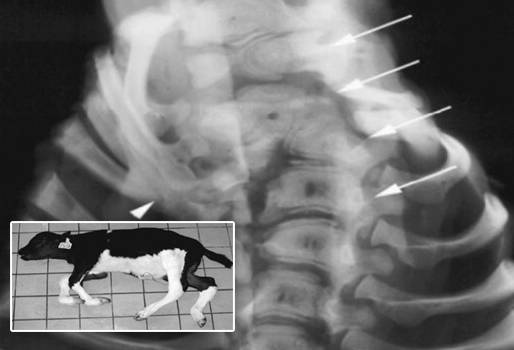

La osteomalacia es una enfermedad que provoca deformidades en partes esqueléticas del cuerpo del animal, además causa anomalías como caminar diferente o malos aplomos, aclaró Carlos Mario Jaramillo, médico veterinario y zootecnista, docente de la Universidad Agraria.

Esta afección, derivada de los cambios químicos biológicos, se origina por la deficiencia de minerales en la alimentación de los animales, como calcio y fosforo, alterando también el cartílago.

Jaramillo apuntó que la osteomalacia se da por una mala fijación de calcio y fosforo, sobre todo de este último, al haber una deficiencia nutricional. Los síntomas que presentan los animales se observan en la dificultad en el caminar o mal aplomo, denominadas como comunmente como rodillijunto o patiapartado; muy abierto de rodillas o abierto de corvejones.

Ángela Mosquera, zootecnista, aseguró que para diagnosticar la osteomalacia, es necesario tomar una muestra de sangre a las vacas y luego enviar al laboratorio, aunque generalmente los bovinos presentan cambios físicos que pueden revelar la afectación que tiene el animal.

Adicional a esto, la profesional dijo que “los bovinos aunque son unos animales muy resistentes, cuando llegan a la etapa aguda de la enfermedad, presentan inflamaciones en los huesos o también los huesos se pueden arquear, se vuelven animales de huesos débiles o se cae mucho; no es firme en su caminar y en su posición”.